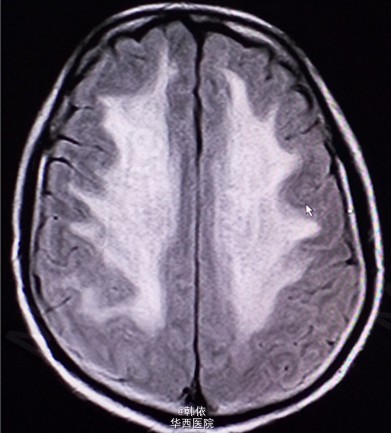

原创:青年男性,因“反复突发意识障碍1+月”入院,1+月前,患者感冒后突发意识障碍,呼之不应,随之出现四肢抽搐,双上肢屈曲、抽搐,双下肢强直,双眼向上凝视,牙关紧闭,小便失禁,无口吐白沫等,持续10+秒后意识恢复,不能回忆,急诊入当地医院治疗,行脑脊液、头部增强MRI等检查,考虑“痫性发作,病毒性脑膜炎”给予降颅内压、抗病毒等治疗,患者住院过程中出现一次右下肢抽动及多次小便失禁,治疗过程中感头部昏沉感,呈持续性,并出现饮水呛咳,治疗效果欠佳。既往患有高血压2+年,未治疗。长期农药接触史2+年。查体:神清,对答切题,高级神经活动正常,双瞳孔等大等圆3mm,对光反射灵敏。四肢肌力肌张力正常,左侧病理征(+),右侧病理征(-),余无特殊。辅助检查:头部MRI示:双侧基底节、双侧丘脑、脑干、双侧小脑及双侧侧脑室旁、双侧半卵圆中心对称性信号异常,考虑中毒性、代谢性疾患可能(见下图)。